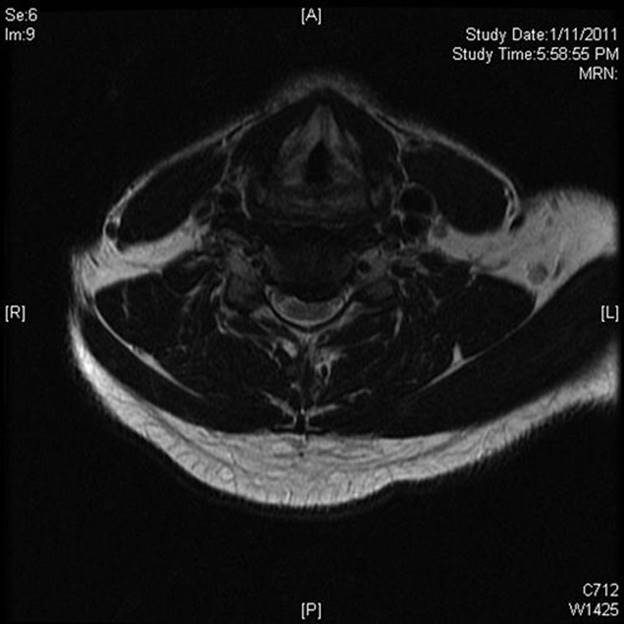

b. An MRI scan without contrast is the study of choice for demonstrating a cervical disc herniation (Fig. 22.1).

FIGURE 22.1 Axial T2-weighted MRI demonstrating a large eccentric cervical disc protrusion (C5–C6) causing impingement on the ventral aspect of the spinal cord and foraminal impingement.